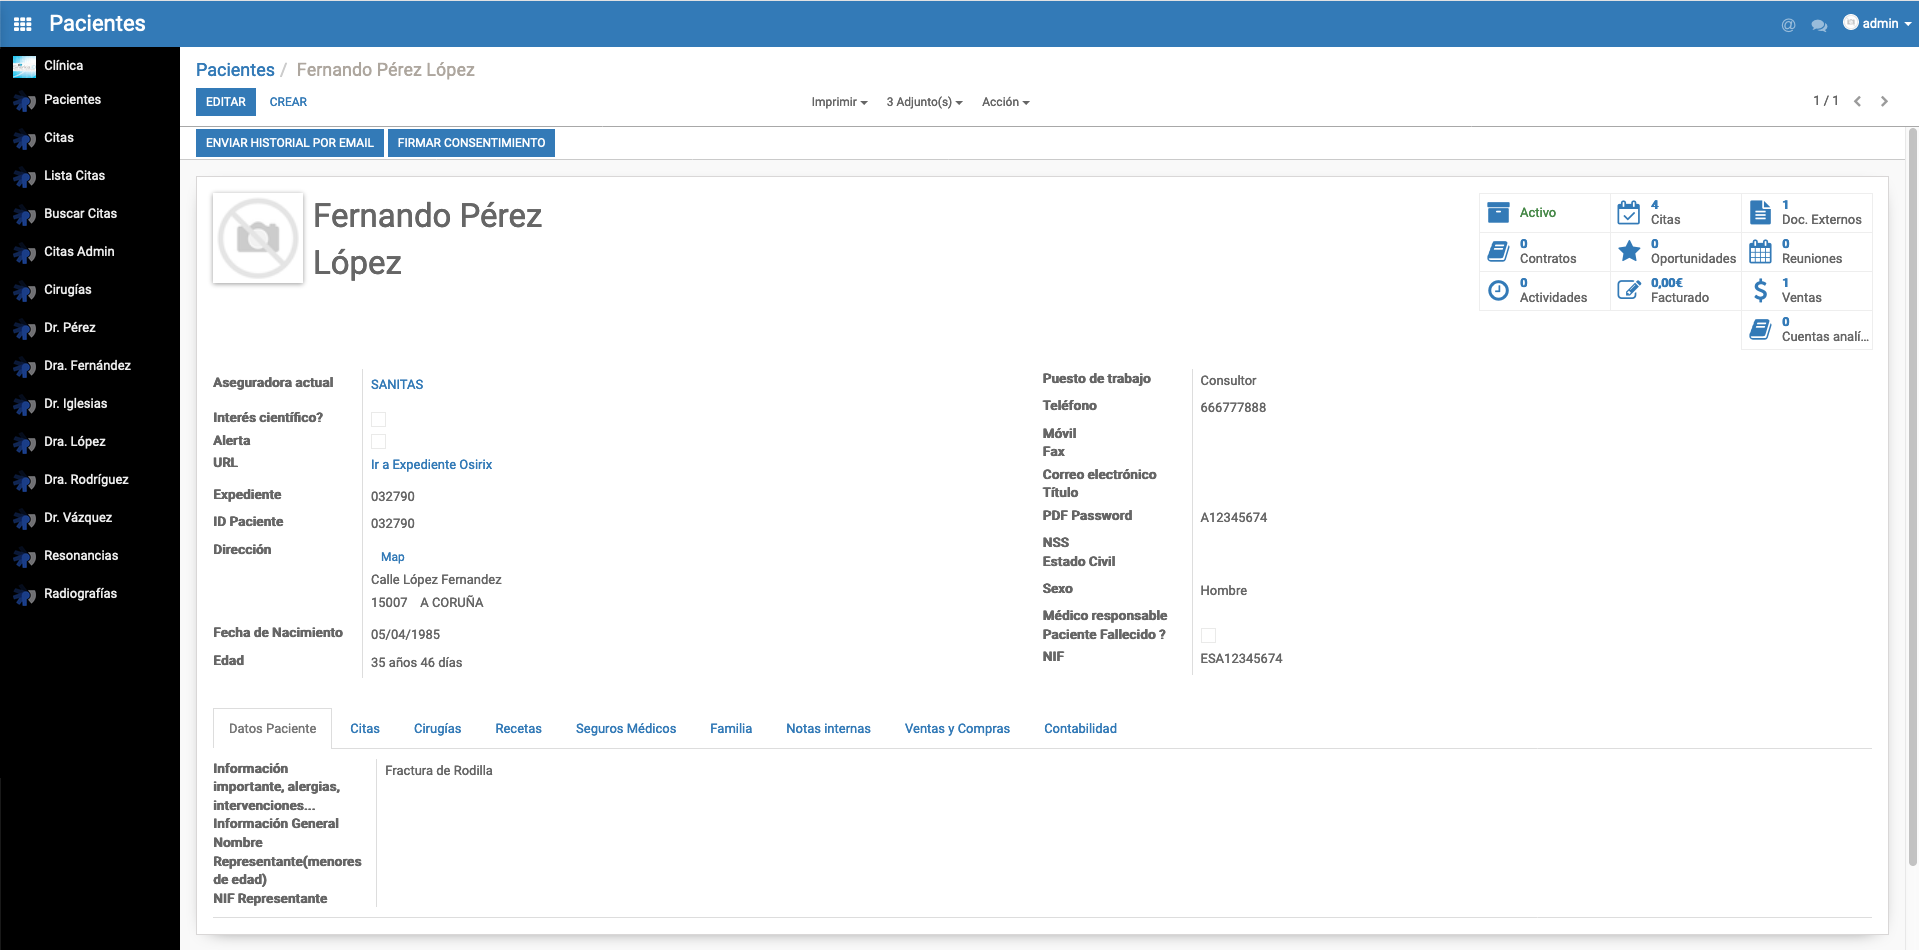

Módulo

Pacientes

Medical Sinerkia proporciona un sistema de gestión de pacientes que facilita obtener en una única vista su historia clínica, proporciona acceso directo a sus citas, recetas, documentos, cirugías y facturas.

Medical Sinerkia se integra con un visor DICOM para tener en una única herramienta toda la información del paciente.